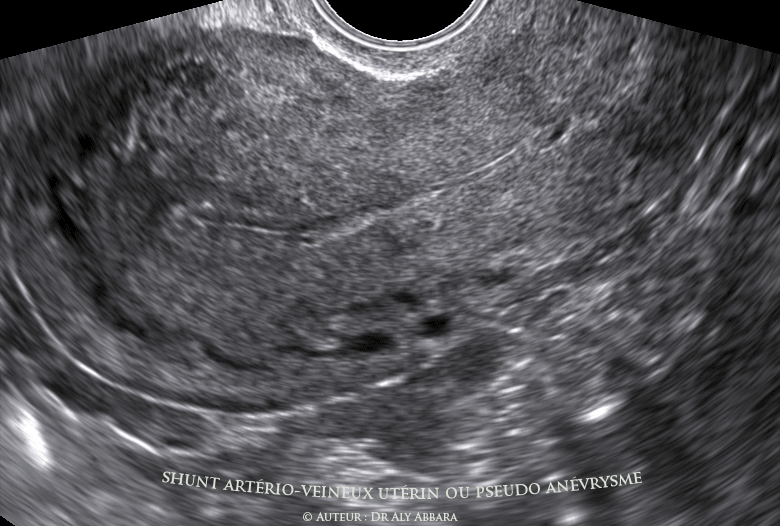

Aspect échographique de l'utérus 40 jours après la réalisation

des premiers vidéos : on observe une régression spontanée du

volume de l'anomalie vasculaire utérine |

des premières images : on observe une régression spontanée

du volume de l'anomalie vasculaire utérine |

- L’échographie réalisée dans la phase proliférative suivante cette deuxième menstruation confirme la normalisation spontanée de l'aspect de l'endomètre ; le Doppler en Flow-Dynamic révèle la persistance du shunt artério-veineux dans le myomètre de la paroi postérieure de l'utérus, mais d'un volume nettement réduit comparé au volume initial, 40 jours auparavant.